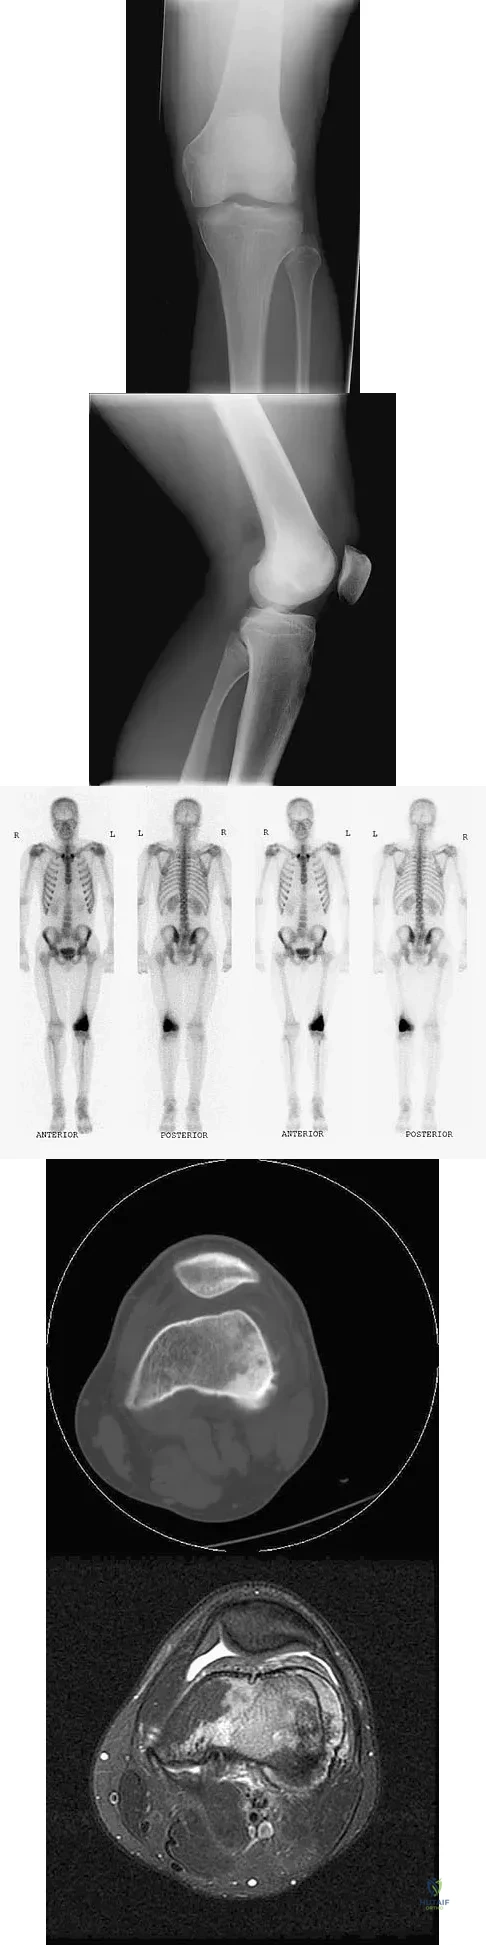

A 19-year-old man has had intermittent progressive knee pain with ambulation and pain at night following a rodeo accident 4 weeks ago. Figures 4a through 4e show the radiographs, a bone scan, CT scan, and T2-weighted MRI scan. What is the most likely diagnosis?

Detailed Explanation